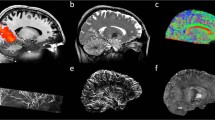

Approval from the regulatory body and ethics committee to perform initial tests in vivo on 20 healthy adult participants was granted early in 2023 to validate the general 11.7-T MRI set-up and safety. Until now, the highest magnetic field used for MRI on humans was 10.5 T, at the University of Minnesota in the United States13. Overall, for small flip angle excitations and large flip angle refocusing pulses, normalized root mean square errors (n.r.m.s.e.) equal or lower than 13% thereby could be obtained at 11.7 T over the whole brain, the latter value being the intrinsic inhomogeneity achieved at 3 T with volume coils14. Inversion pulses remained difficult to achieve given the architecture of the coil, leaving very localized artifacts despite reaching 8% n.r.m.s.e. Static B0 shimming was performed up to second order for each participant, using a brain mask and a quadratic programming approach yielding on average 82.7-Hz standard deviation over the brain (0.17 ppm). After B0 and RF field mapping for each participant, following the RF pulse designs T2 and T2*-weighted acquisitions were performed by deploying parallel transmission techniques (Fig. 2). The presented in vivo human brain images acquired at 11.7 T reveal good signal homogeneity consistent with the simulations, without severe RF field inhomogeneity artifacts. A 2D T2*-weighted acquisition was repeated at 3 and 7 T on different participants to reach similar contrast-to-noise ratio at the three field strengths, while keeping similar acquisition times, showing the gain in spatial resolution when increasing the field (Fig. 2c) and details around the calcarine fissure and within the cerebellum. Details within the cortical ribbon become clearly visible at 11.7 T and not at lower field strength due to poorer spatial resolution. Another approach was to keep the same protocol parameters (resolution, bandwidth, acquisition time, number of receive elements and so on) to visualize the signal to noise ratio (SNR) gain brought by field strength (Extended Data Fig. 1).

a, In vivo 3D T2 variable flip angle turbo spin-echo acquisition at 11.7 T with parallel transmission GRAPE universal pulses (resolution 0.55 × 0.55 × 0.55 mm3, acquisition time 13 min) demonstrating the high B1+ (RF) field homogeneity reached throughout the whole brain volume. b, In vivo T2*-weighted 2D GRE sagittal slice (resolution 0.2 × 0.2 × 1 mm3, acquisition time 8 min 30 s). c, T2* weighted 2D GRE axial images acquired at 3 T (left), 7 T (middle) and 11.7 T (right) with identical acquisition times (4 min 17 s), while keeping similar contrast-to-noise ratio through adjusted acquisition parameters (FA (°), TR (ms) and TE (ms) of 27, 750 and 45; 34, 950 and 25; 27, 600 and 20 at 3, 7 and 11.7 T, respectively) and spatial resolution (0.5, 0.325 and 0.2-mm in-plane resolution for 3, 7 and 11.7 T, respectively, 1-mm thickness). d, The 11.7 T T2*-weighted 2D GRE axial images (resolution 0.19 × 0.19 × 1 mm3, acquisition time 5 min 16 s) juxtaposed to turbo spin-echo T2-weighted images (resolution 0.3 × 0.3 × 1 mm3, acquisition time 4 min 26 s).